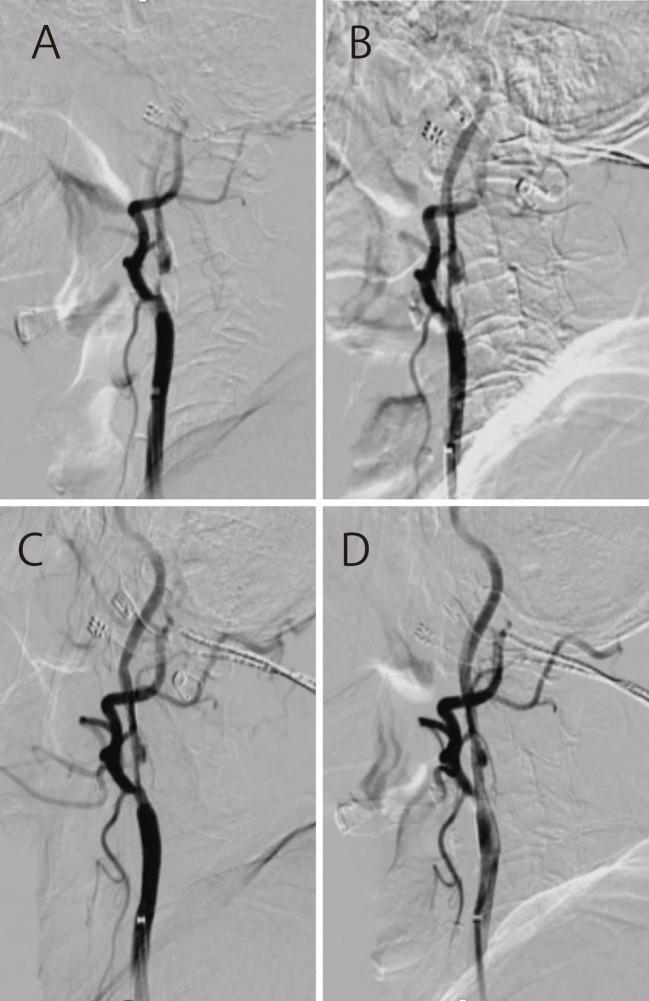

Most previous large studies of carotid artery stenting (CAS) in maintenance hemodialysis patients are old-era, do not describe the types of stents and method of protection, and their effectiveness is unknown. CAS has progressed remarkably, and tailor-made CAS is now possible in hemodialysis patients according to the lesion. We aimed to analyze the outcomes of CAS in maintenance hemodialysis patients treated in our institution.We retrospectively investigated the data of patients who underwent elective CAS in our institution between January 2012 and April 2023. Firstly, we verified the outcomes of CAS in maintenance hemodialysis patients. Secondly, the outcomes of CAS in maintenance hemodialysis patients were compared with CAS in nondialysis patients during the same period.During the study period, 212 patients with carotid stenosis underwent CAS. Among these, 18 patients undergoing maintenance hemodialysis were identified for analysis. All 18 patients underwent lesion-specific tailor-made CAS. All 18 patients were technically successfully stented with good vasodilation and improvement in stenosis. No symptomatic cerebral infarction occurred within 30 days after CAS. There was no difference between dialysis and nondialysis patients in the risk of symptomatic complications and death occurring within 30 days after surgery. There was a higher risk of hemorrhagic complications not associated with prognosis in the dialysis group (23.1% vs 1.0%, P = 0.0047). No in-stent restenosis (>50% stenosis) and ipsilateral cerebral infarction at 1 year occurred during follow-up.CAS in hemodialysis patients may be safe and effective.

以往对维持性血液透析患者进行颈动脉支架置入术(CAS)的大型研究大多年代久远,未对支架类型和保护方法进行描述,其效果也不得而知。目前,CAS 已取得显著进展,可根据病变情况为血液透析患者量身定制 CAS。我们回顾性调查了 2012 年 1 月至 2023 年 4 月期间在我院接受选择性 CAS 治疗的患者数据。首先,我们核实了维持性血液透析患者接受 CAS 治疗的结果。在研究期间,212 名颈动脉狭窄患者接受了 CAS。在研究期间,212 名颈动脉狭窄患者接受了 CAS 手术,其中 18 名接受维持性血液透析的患者被确定为分析对象。所有 18 名患者都接受了针对病变部位量身定制的 CAS。所有 18 名患者都成功地进行了技术性支架置入,血管扩张良好,狭窄情况有所改善。CAS 术后 30 天内未发生无症状脑梗塞。透析患者和非透析患者在术后30天内出现症状性并发症和死亡的风险没有差异。透析组发生与预后无关的出血性并发症的风险较高(23.1% vs 1.0%,P = 0.0047)。随访期间没有发生支架内再狭窄(狭窄程度大于50%)和同侧脑梗死。